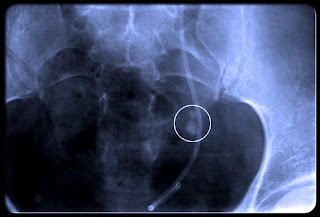

يشك الطبيب في جود حصوه من الاعراض السابق ذكرها بعد استبعاد الاسباب الاخري لمثل هذه الالام . ولكن يقوم الطبيب بعمل أشعه تلفزيونيه على منطقه البطن فيما يعرف بالسونار ومن خلال ذلك يستطيع ان يرى الحصوات بوضوح .. او عمل أشعه مقطعيه لمنطقه البطن ..

الحصوه 4 مم لديها فرص 80% للمرور .. والحصوه 5 مم لديها فرص 20 % للمرور واكبر من ذلك فانه من الصعب المرور ..